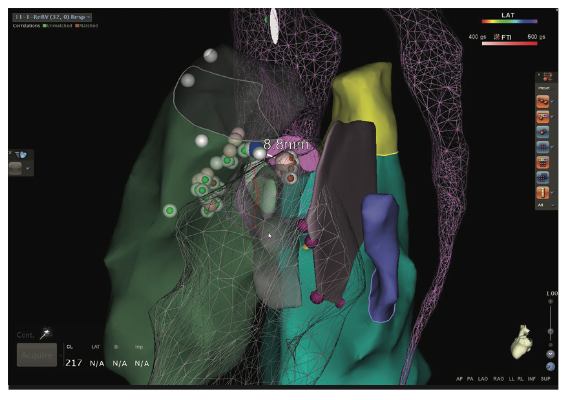

Videos 13a-b and Figure 13c demomstrate a zero fluoroscopic ischemic, incessant, hemodynamically tolerated VT ablation and creation of a 4-chamber EAM/sound map and a figure-of-8 VT in a patient with a large anteroapical infarction along with the electrogram resolution afforded by small 1-mm electrodes of the Pentaray in the isthmus corridor.